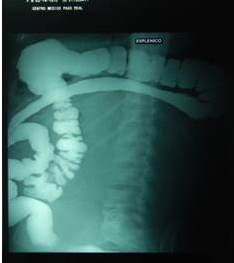

- Tránsito intestinal: desplazamiento medial de colon y asas hacia el hemiabdomen derecho (Figura 3).

Generalmente la exploración se inicia con el ultrasonido abdominal y la radiografía de abdomen simple, estudios poco específicos. En la radiografía simple podemos evidenciar signos sugestivos de una tumoración: aumento de la densidad, desplazamiento o alteración de la sombra renal, desplazamiento de las asas intestinales, calcificaciones, borramiento de la línea del psoas. La radiografía de tórax de gran ayuda para identificar la existencia de metástasis pulmonar (10). El ultrasonido permite distinguir la naturaleza de la lesión (sólida o quística), su volumen, topografía y relación con los vasos (11). Como se ve en el caso presentado, se sigue el protocolo de estudio.